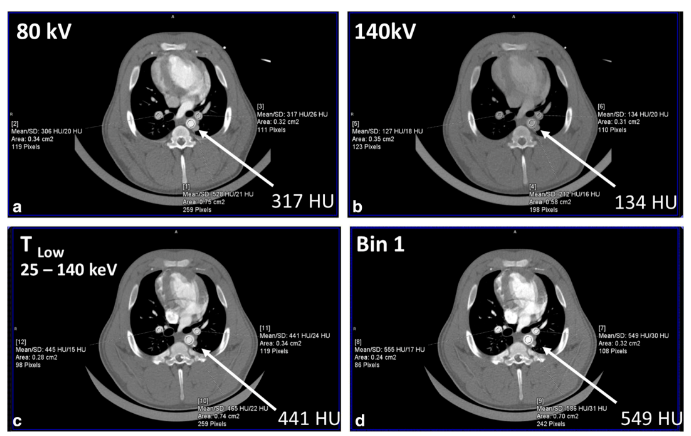

低能量X射线(如小于40-50 keV)具有显著的组织对比度信息,尤其是来自碘和骨骼的信息。然而,与高能量X射线相比,EID在这些低能量下产生的信号值较低。不幸的是,高能量光子几乎不携带组织对比信息,却能产生最多的信号。由于PCD会对每个光子进行计数,并将其分配到各个能量箱中,因此所有光子的权重都相同,与能量无关。因此,相对于EID,低能量光子对PCD的贡献更大,从而改善了图像对比度和对比噪声比(图4)。除了这一基本优势外,由于X射线是根据其能量进行分档的,因此用户可以在采集后为各个能量分档分配自定义权重,从而提高图像对比度。

图4 上图是在80 kV和140 kV电压下扫描的猪的EID-CT图像,显示在较高的管电压下碘对比度大幅下降。下图是在140 kV电压下扫描的同一动物的PCD-CT图像。在低能量阈值图像(TLow)中,主动脉中的碘信号(箭头)更高,该图像包含25到140 keV的光子。包含25至65 keV光子的1号仓图像具有最高的碘信号,甚至比EID-CT系统在80 kV电压下获得的碘信号更亮。